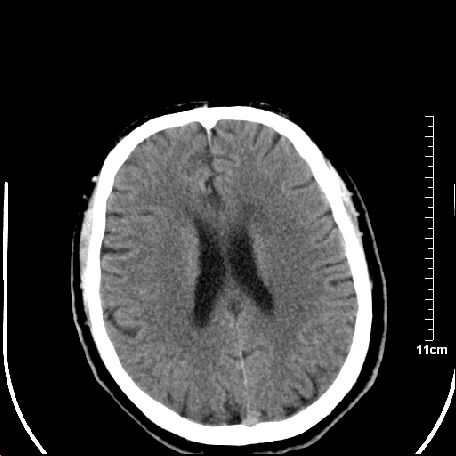

外伤患者,什么病,

外伤患者,没什么症状,

双侧外侧裂,左侧脑沟见高密度结节影,边清,还有鞍上池层面密度也高

1.左额叶脑软化灶。

2.老年脑,基底动脉硬化迂曲。

基底动脉硬化迂曲。高血红蛋白血症。